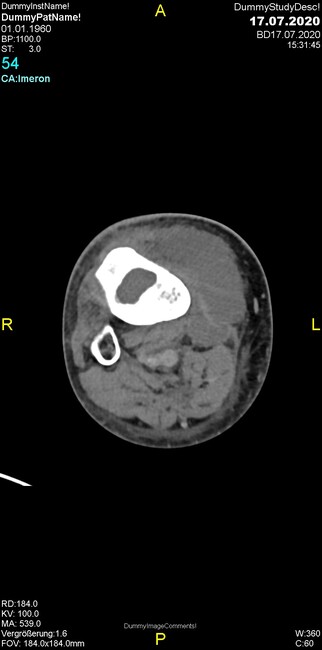

Um welche Modalitäten handelt es sich?

- Röntgen p.a. und lateral, CT coronar Knochenfenster, CT axial Weichgewebsfenster

- Röntgen p.a. und oblique, CT coronar Knochenfenster, CT axial Weichgewebsfenster

- Röntgen p.a. und lateral, CT sagittal Weichgewebsfenster, CT coronar Knochenfenster

- Röntgen p.a. und oblique, CT sagittal Knochenfenster, CT coronar Weichgewebsfenster

- Röntgen p.a. und lateral, CT coronar Weichgewebsfenster, MR axial

Was fällt in der CT im Knochenfenster auf?

- Mediale Gelenkspaltverschmälerung

- Dezente Erosion der fibulären Kortikalis

- Frakturspalt der lateralen Tibiametaphyse

- Weichgewebskalzifikationen lateral angrenzend an den Gelenkspalt

- Osteolyse der Tibiametaphyse unter Beteiligung der Kortikalis

Was kommt differentialdiagnostisch in Frage?

- Kompartmentsyndrom

- Osteomyelitis mit Weichgewebsanteil

- Metastase mit pathologischer Fraktur

- Rheumatoide Athritis

- Posttraumatische Verletzung